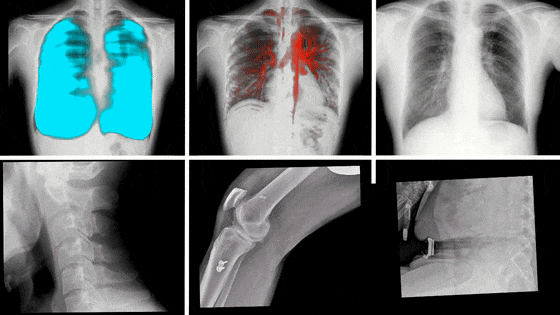

動態DR影像

隨著科學技術的不斷發展,動態DR在未來還將擁有更多的發展空間,在更多領域得到應用,如兒科、骨科、呼吸科等,為更多患者提供高質量的醫療服務。